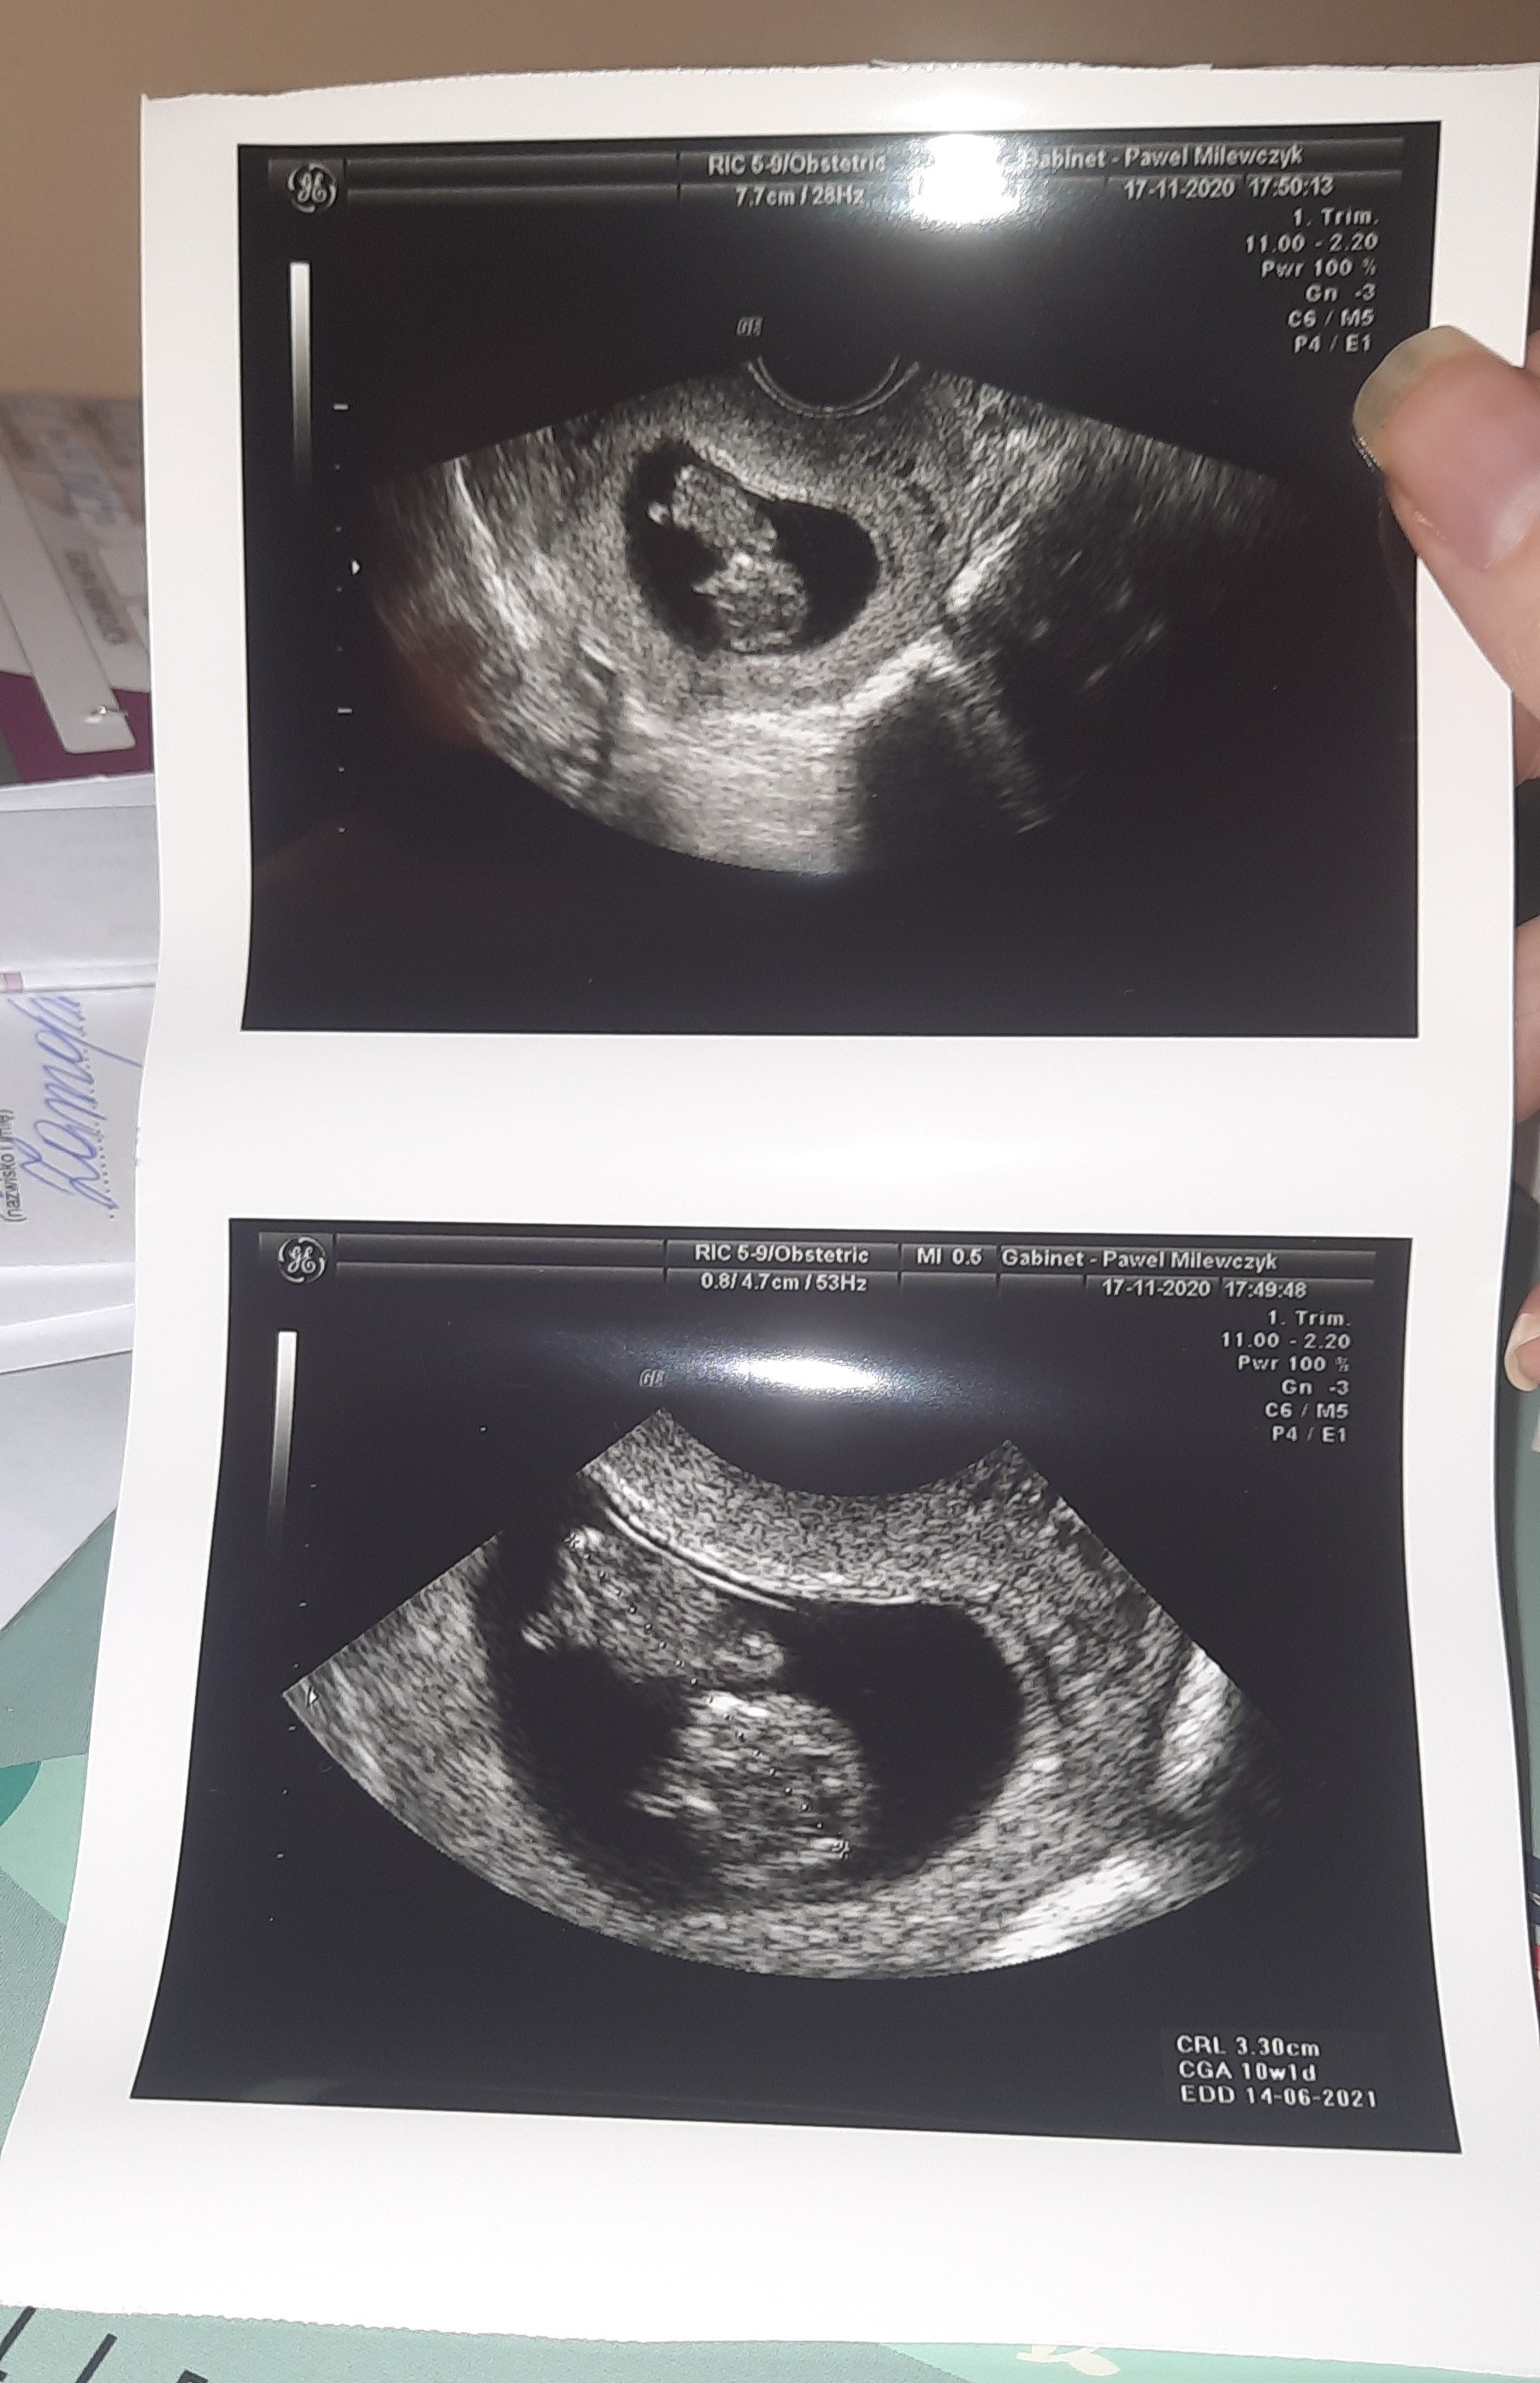

Miało byc 2.12 u prowadzacego28 prenatalne i 2 kontrolna u prowadzacego![]()

Wizytę odwołałam, mam taki ból pleców, że wstać nie mogę. Nie wiem czy to covid się odzywa. Ale podobnie miałam w czerwcu. No masakra. Jak do jutra nie przejdzie, to się nie bawię już i jadę na izbe przyjęćTrzymam kciuki za dzisiejszą wizytę. Myślałam, że mamy ten sam tydzień, ale u mnie już 10.

Jestem Mamą 3 latka, obecnie w 10 tc, termin przypada na 11.06![]()

To tak jak u mnieCzesc ☺ bardzo blisko mnie ja na 13.06 ☺ ta trzynastka za mna chodzi![]()